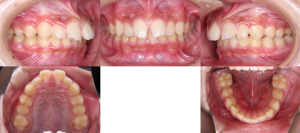

※初診時口腔内写真(全体)

初診時の状態では、上下のいちばん奥の歯がまだ生えそろっていない段階でした。

また、上の前歯が前方に出ている噛み合わせの傾向が見られました。